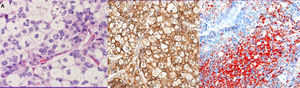

Se realizó una mamografía y ecografía, mostrando una masa irregular de 18mm sin conexión con la piel o el pezón (BIRADS5) (fig. 1A y B).

Se practicó biopsia con aguja gruesa guiada por ecografía con el resultado de carcinoma infiltrante de tipo común, grado histológico II (B5b). Se indicó cirugía y, de acuerdo con el paciente, se realizó una mastectomía derecha simple con biopsia selectiva del ganglio centinela axilar. Macroscópicamente el tumor era blanquecino de 1,4cm, nodular, no conectado con la piel o el pezón suprayacente. Microscópicamente, el tumor estaba constituido por células pequeñas, con núcleos redondos y nucléolos generalmente únicos, con amplios citoplasmas claros microvacuolados (fig. 2A). La inmunotinción del antígeno de membrana epitelial (EMA) fue positiva (fig. 2B). El tejido fresco contenía citoplasma lipídico que fue positivo para el rojo oleoso (fig. 2C). El componente sebáceo representaba más del 50% del tumor. La inmunohistoquímica de células tumorales reveló positividad para los receptores de estrógeno (RE) (fig. 3A), los receptores de progesterona (RP) (fig. 3B) y los receptores de andrógeno (RA) (fig. 3C y D). La proliferación de Ki67 fue del 30-35% (fig. 3F) y el HER2 fue negativo (fig. 3E).